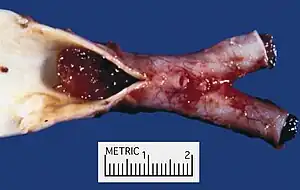

Atrial myxoma covered by endothelium. H&E stain.

Atrial myxoma covered by endothelium. H&E stain.